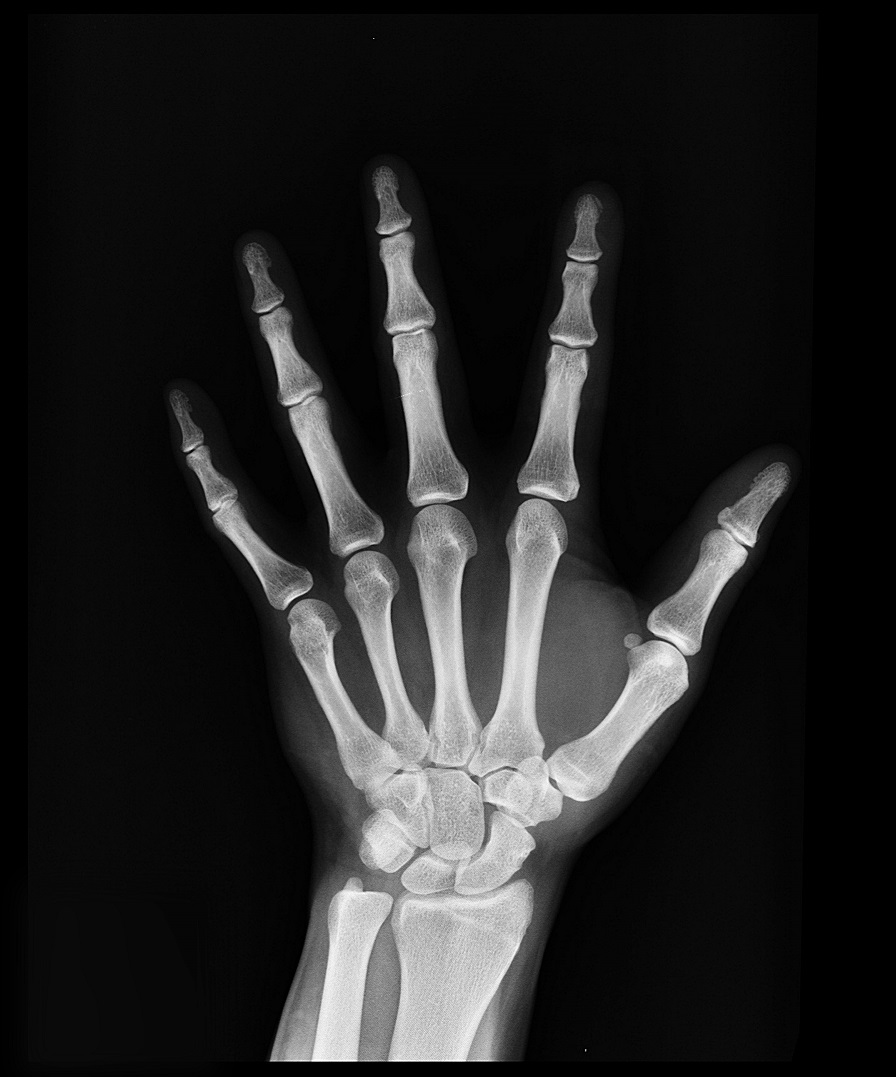

També se sol·licita una radiografia de canell que ens ajuda a veure el grau de maduració òssia i es compara amb un atles amb radiografies d'altres nens de la mateixa edat.

En el noi la pubertat retardada és més freqüent que en la noia, i la seva causa més freqüent és el retard constitucional del creixement i desenvolupament. Sovint s'acompanya d'un creixement lent previ i una edat òssia (radiografia de canell) retardada. Hi sol haver antecedents en el pare i/o germans.